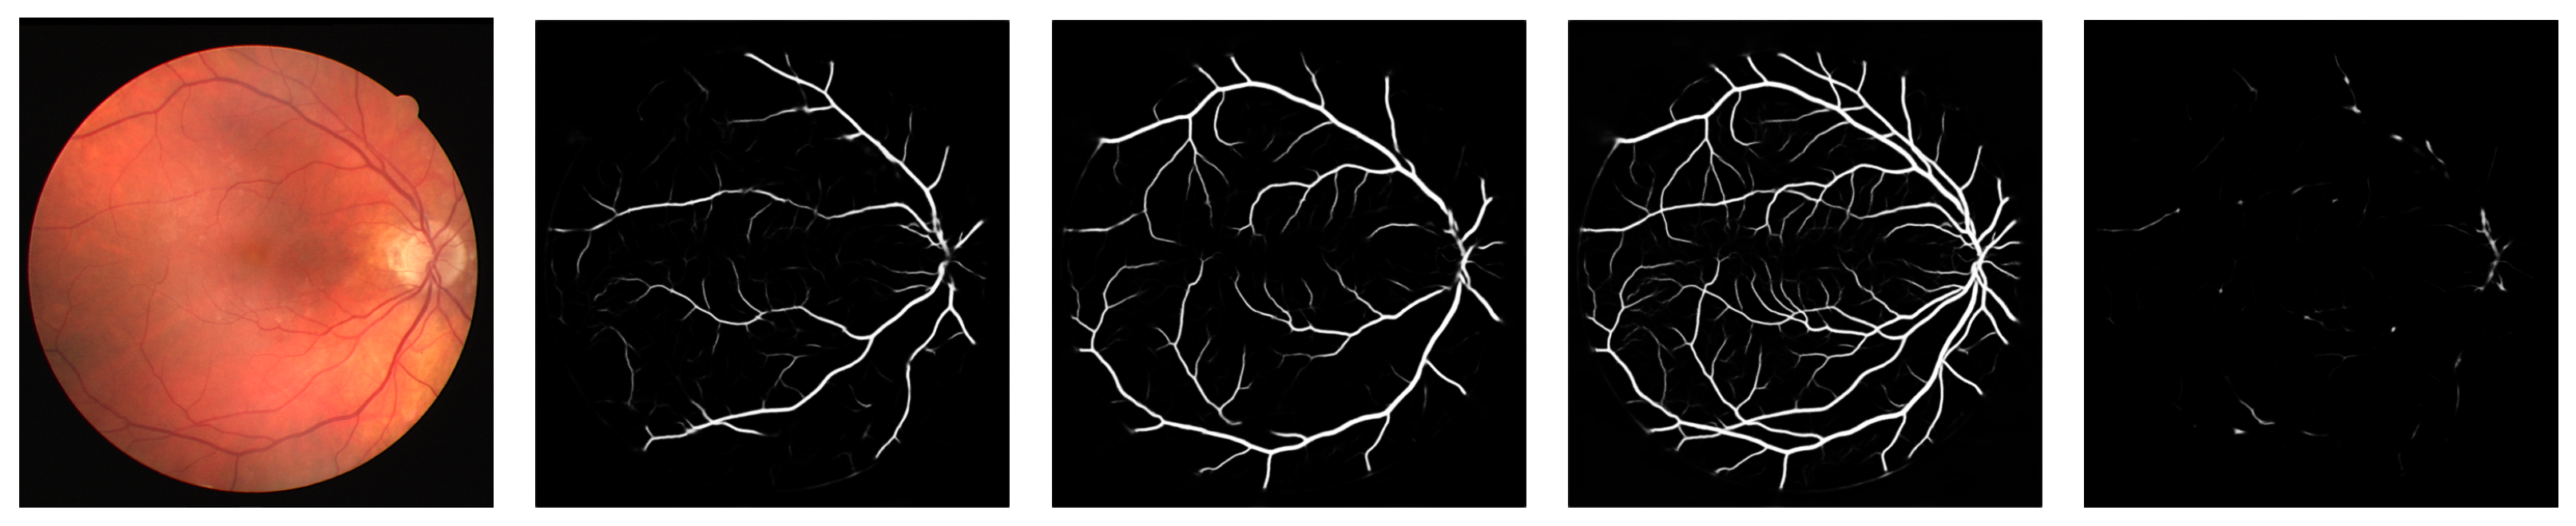

Figure 1 shows an example of an RITE retinography and its arteries, veins, vessels and crossings segmentation maps predicted by a model trained using the MS approach. Figure 2 shows the details of the arteries, veins and vessels segmentation maps of the same retinography predicted by a model trained using the MS and the traditional approaches.

Figure 1.

Example segmentation maps predicted by a model trained using the MS approach. From left to right: arteries, veins, vessels and crossings.